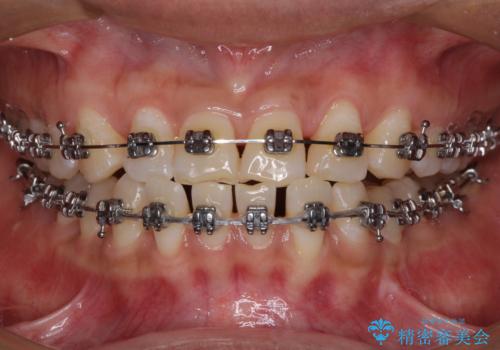

- 矯正装置

- メタルブラケット

咬合力が強く、反対咬合の改善に時間がかかりましたが、その後はスムーズに進めることができました。

途中、妊娠と出産があり、治療が中断したため、治療期間は延びましたが、出産も矯正治療も無事に終えることができました。